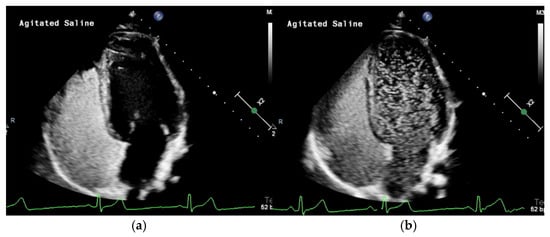

3.1. Transthoracic Contrast Echocardiography with Agitated Saline (TTCE)